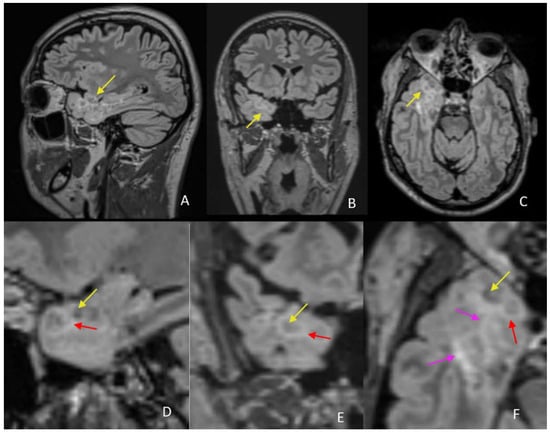

New Imaging Features of Multinodular and Vacuolating Neuronal Tumor Revealed by Alcohol and Illicit Drugs Consumption

Sirbu, C.A.; Ștefani, C.; Tuță, S.; Manole, A.M.; Sirbu, O.M.; Ivan, R.; Toma, G.S.; Calu, A.G.; Jianu, D.C. New Imaging Features of Multinodular and Vacuolating Neuronal Tumor Revealed by Alcohol and Illicit Drugs Consumption. Diagnostics 2022, 12, 2779. https://doi.org/10.3390/diagnostics12112779